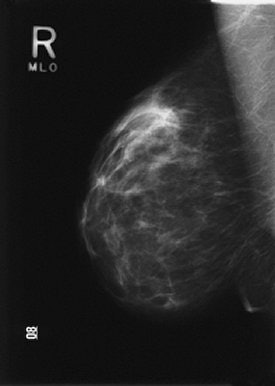

Above, left mediolateral oblique view (MLO) using MammoPad. Below, right MLO without cushioning pad. Images courtesy of BioLucent.